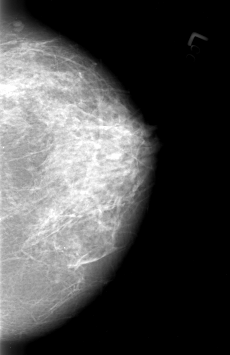

Volume: cancer_01 Case: B-3012-1

B_3012_1.RIGHT_CC

RIGHT_CC LINES 4136 PIXELS_PER_LINE 3152 BITS_PER_PIXEL 12 RESOLUTION 50 OVERLAY

FILE: B_3012_1.RIGHT_CC.OVERLAY

TOTAL_ABNORMALITIES 1

ABNORMALITY 1

LESION_TYPE MASS SHAPE IRREGULAR-ARCHITECTURAL_DISTORTION MARGINS SPICULATED

ASSESSMENT 4

SUBTLETY 3

PATHOLOGY MALIGNANT

TOTAL_OUTLINES 1

BOUNDARY